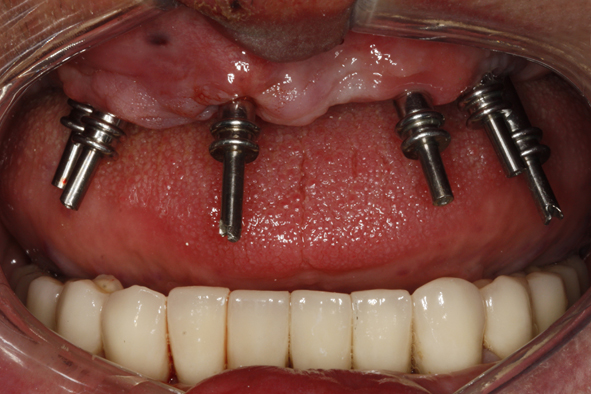

18. Wprowadzenie 4 implantów w odcinku przednim żuchwy – Odbudowa protetyczna na implantach

21. Transfery wyciskowe przykręcone do implantów – zęby własne opracowane jako filary pod korony całoceramiczne – skoagulowane dziąsło brzeżne